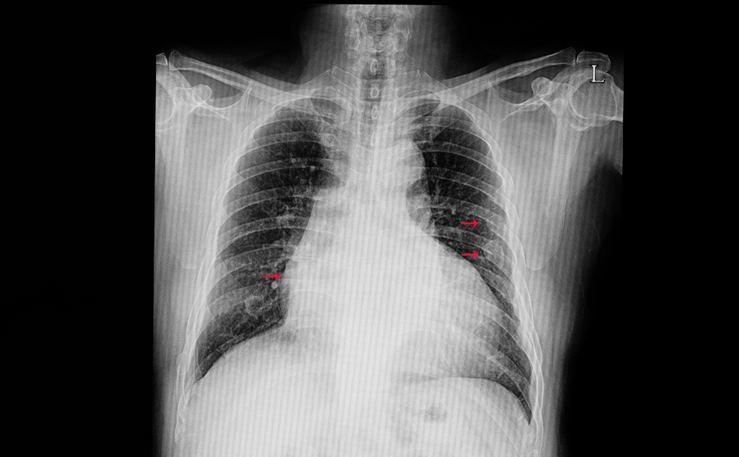

- 3- Dermansızlık : Her zaman,her vakit sık sık kendinizi yorgun ve güçsüz hissediyorsanız bunun sebebi akciğerinize yeterli miktarda k-anın ulaşmamasıdır. Kronik olarak yorgunluk yaşayan kişilerin kalp krizi riski oldukça yüksektir.

- 4- Solunum Sıkıntısı : Kalp krizi gerçekleşmeden önce solunum sıkıntısı ve nefes almakta zorluk çekersiniz. Bunun en mantıklı sebebi ise damarlarınız tıkanık olduğundan dolayı akciğerinize k-an gitmemesidir.